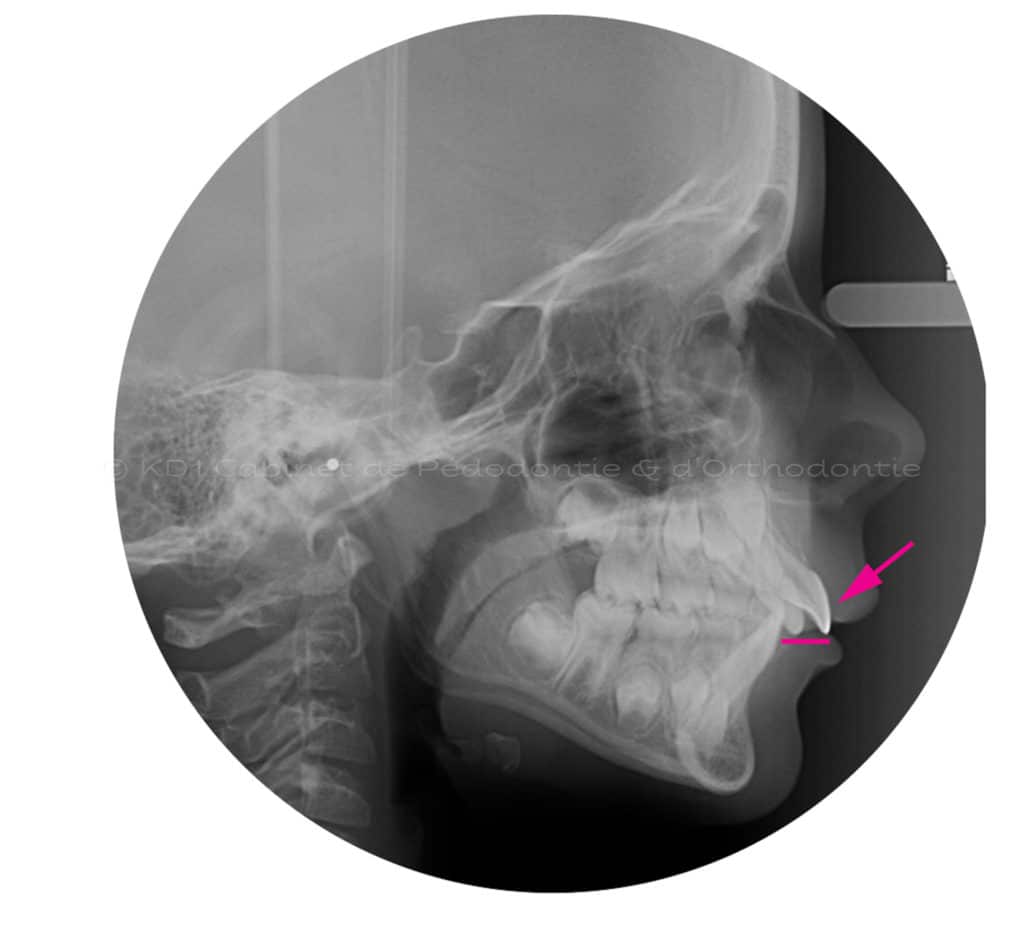

Cas #1 – Traitement avec un casque de traction maxillaire en dentition mixte (âge 8.5). Le but est de redresser les dents de devant (très penchées en avant) afin d’éviter les cassures de ces dents. Le recul de la dentition supérieure est possible avec ce dispositif extraoral.